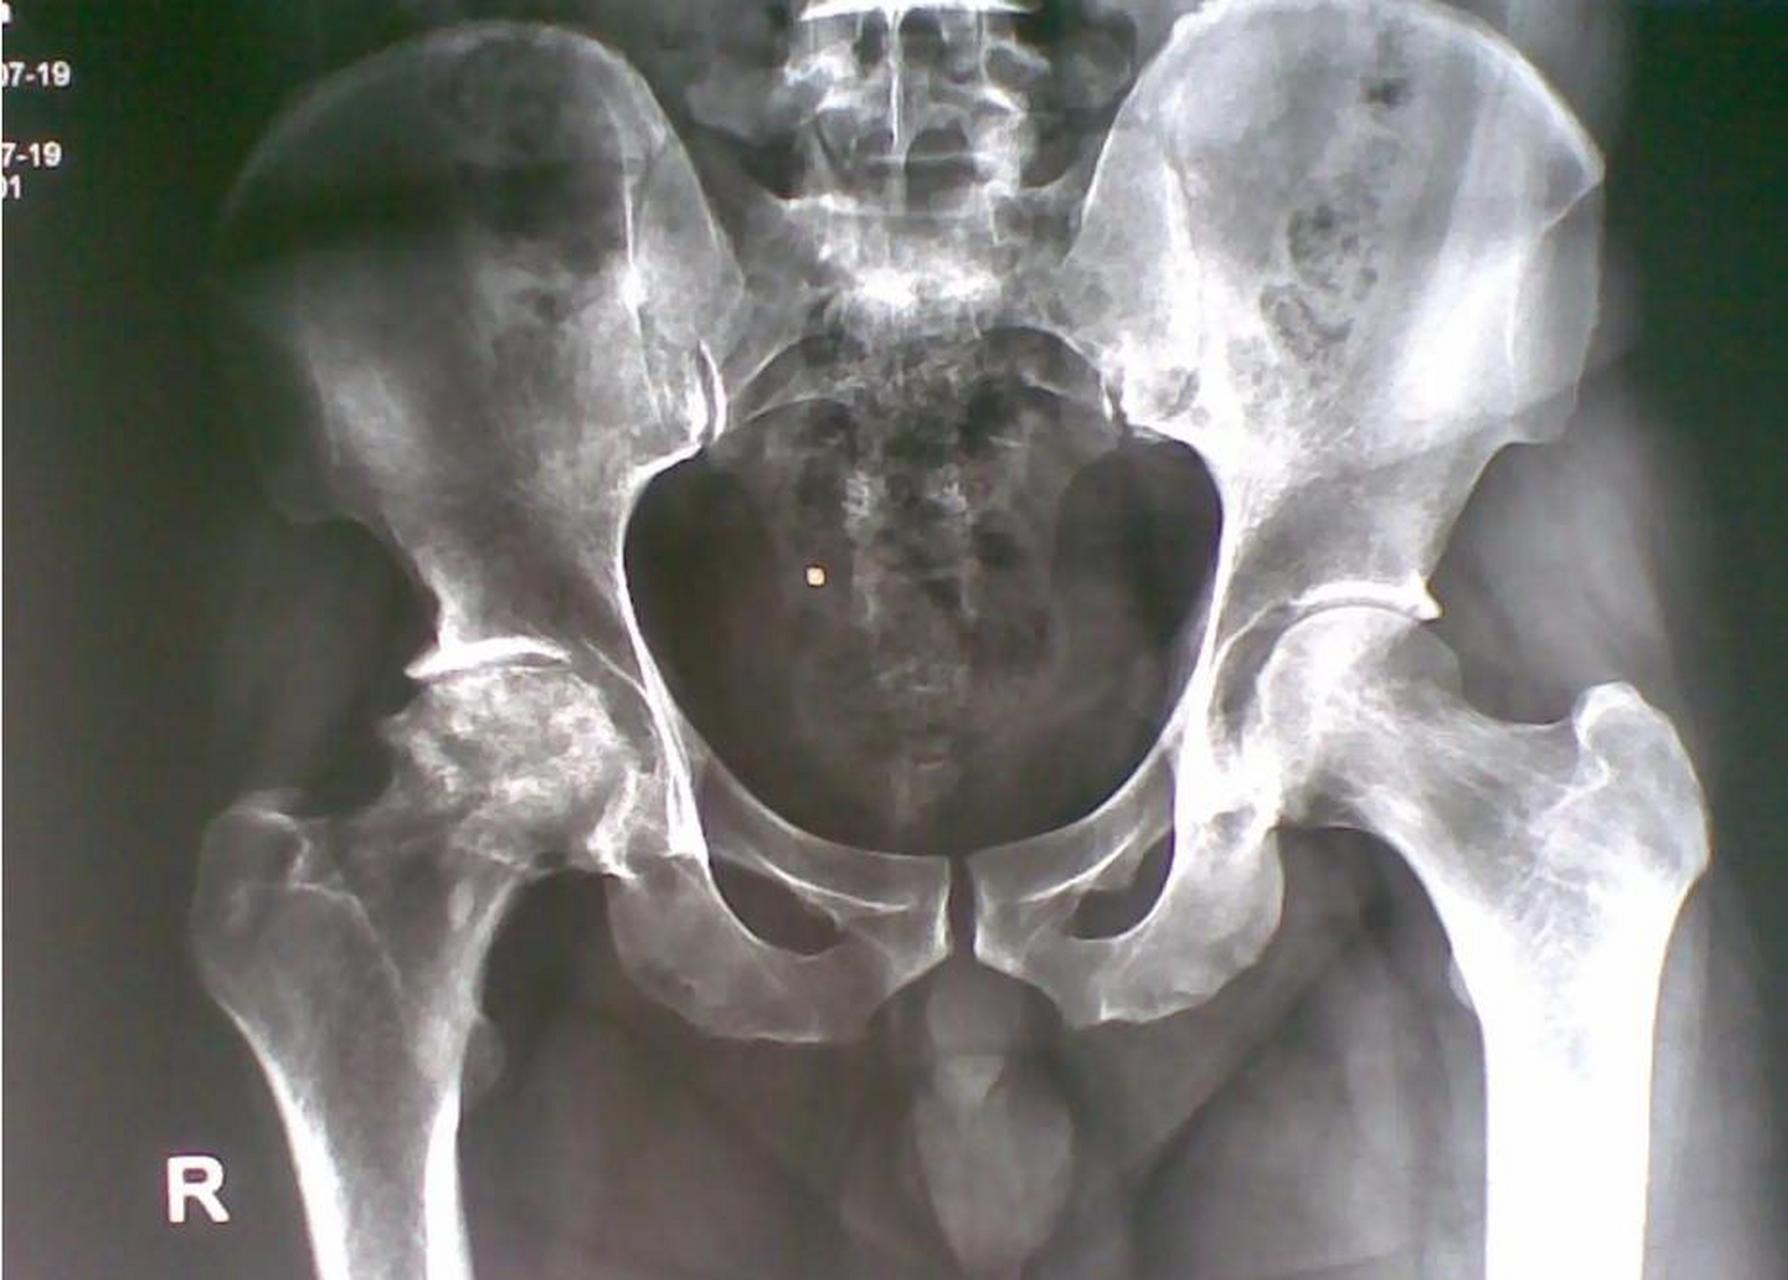

股骨头坏死片子

激素药引起的股骨头坏死,目前发现一侧塌陷